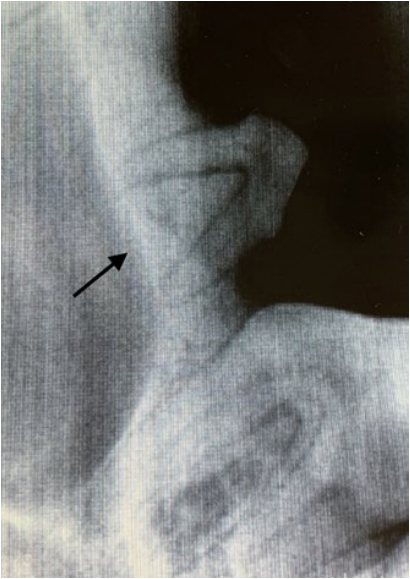

В случаях, когда постоянный зуб прорезывается неестественным путем или его зачаток располагается таким образом, что не может запустить процесс разрушения временного зуба, он прорезывается рядом. В результате смены зуба не происходит (за исключением процесса боковой резорбции, возникающей не на верхушке корня зуба, а на боковой поверхности временного корня, когда зубы находятся в плотном боковом контакте) (фото 1).

- Неправильная траектория прорезывания (фото 2). Такая патология может возникать из-за нарушения развития альвеолярного отростка в результате какого-либо механического препятствия, нарушения закладки зачатков зубов в раннем эмбриональном периоде, а также по причине дефицита места.